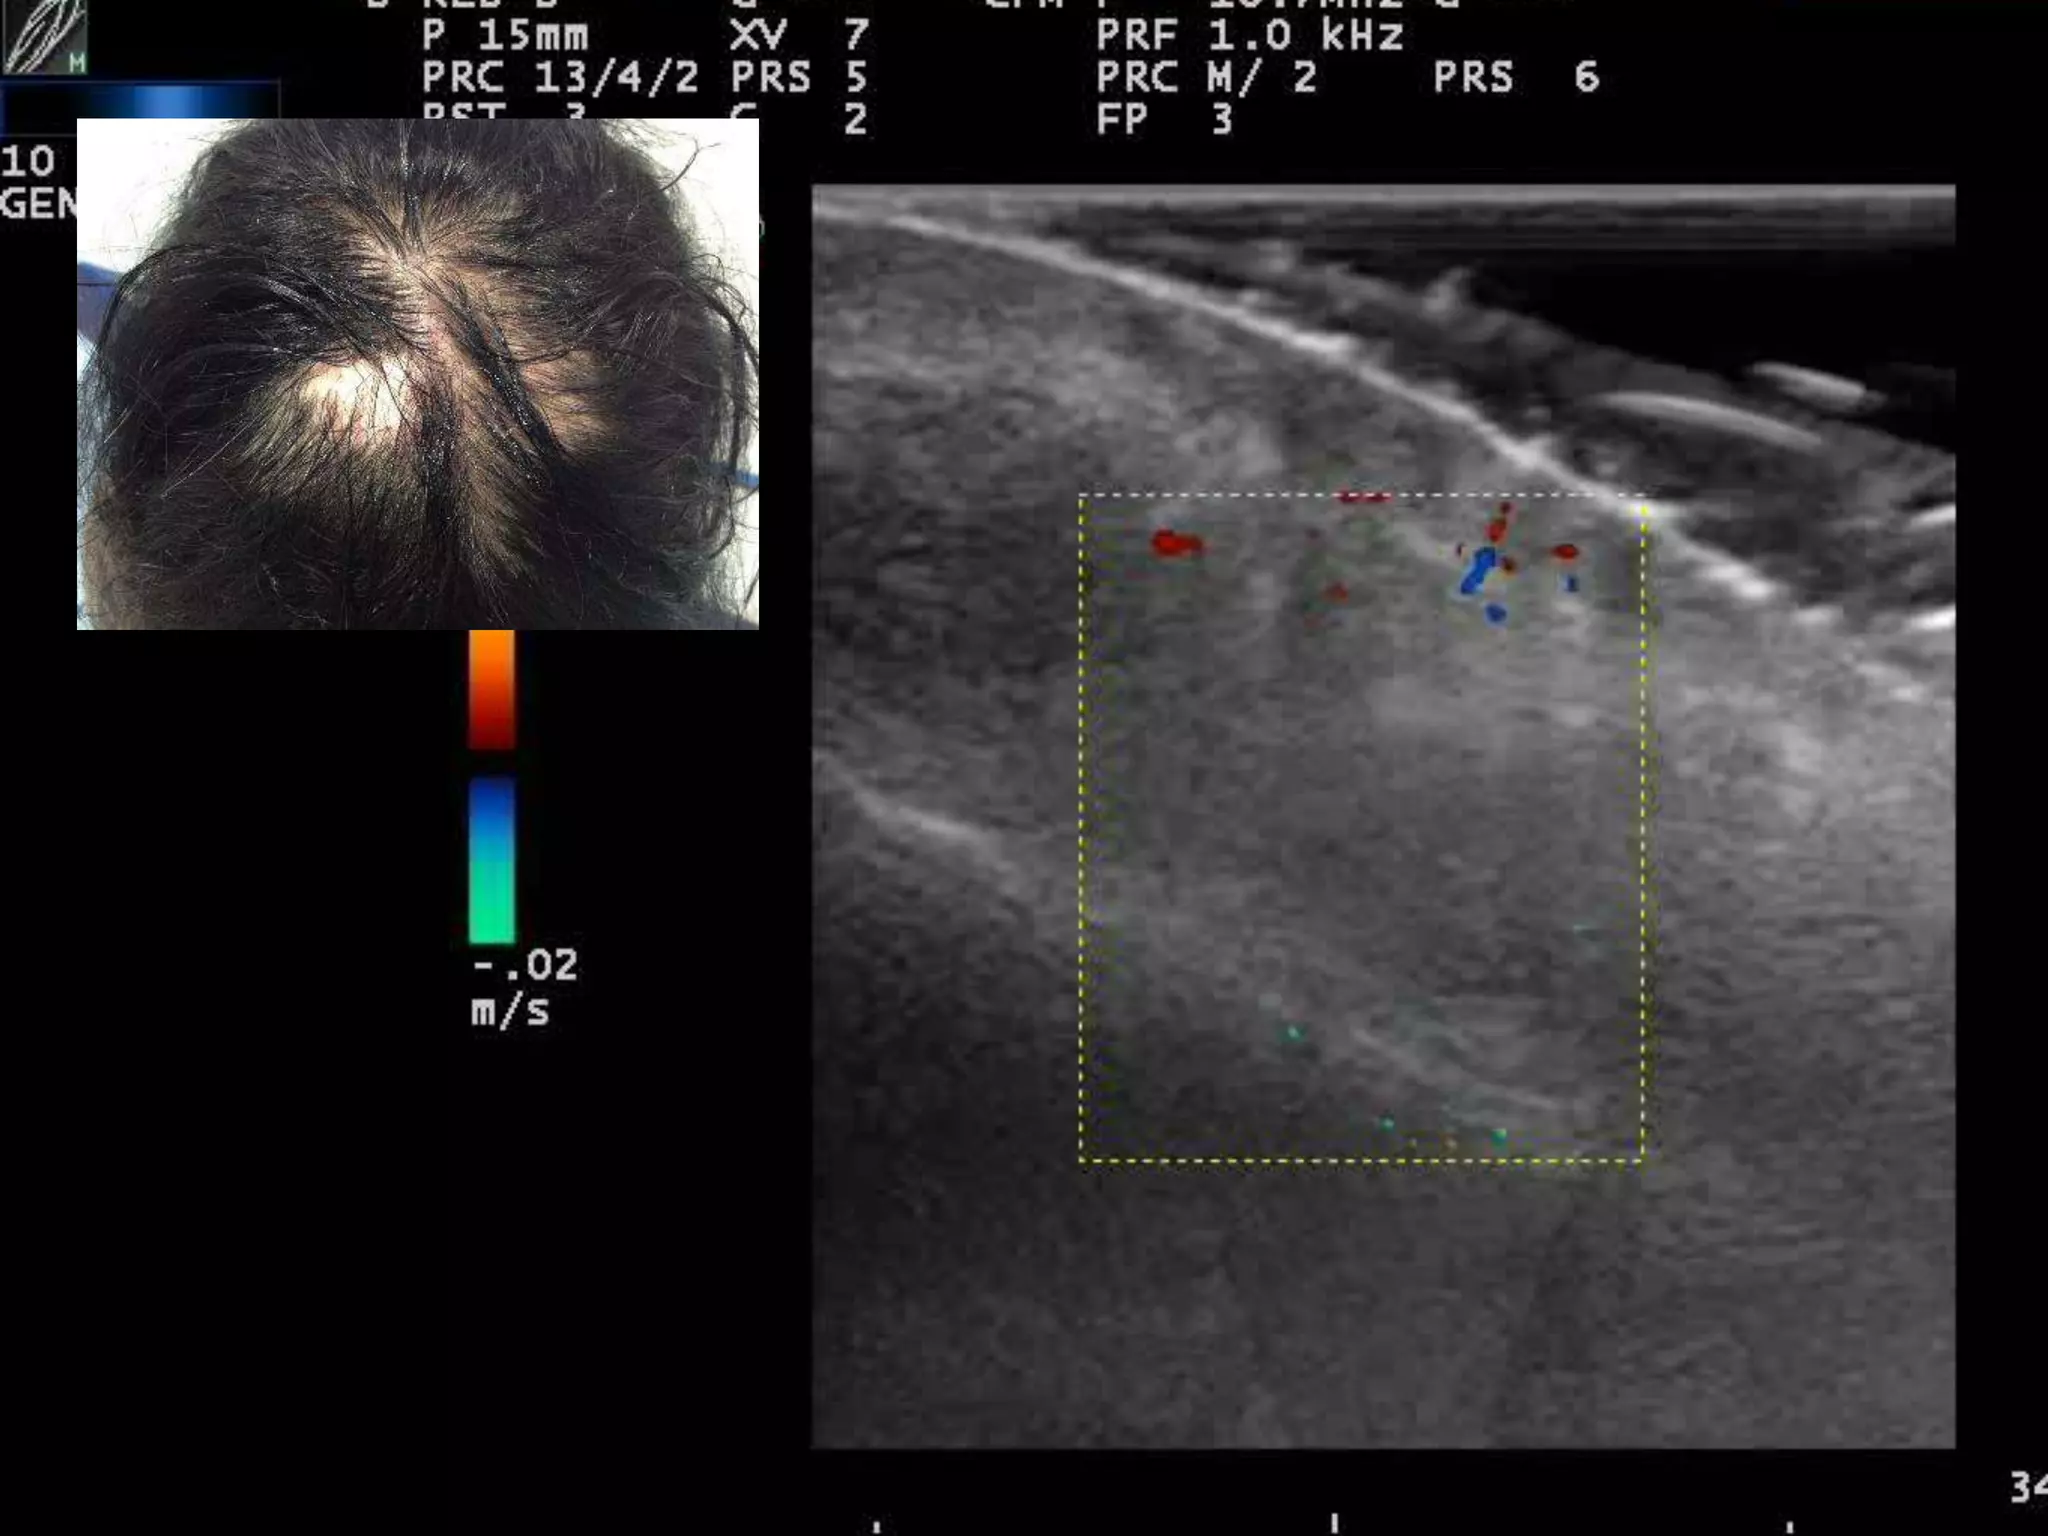

CUERO CABELLUDO

INFLAMADO

LOCALIZACION DE INFLAMACION

FOLICULAR

TINEA CAPITIS